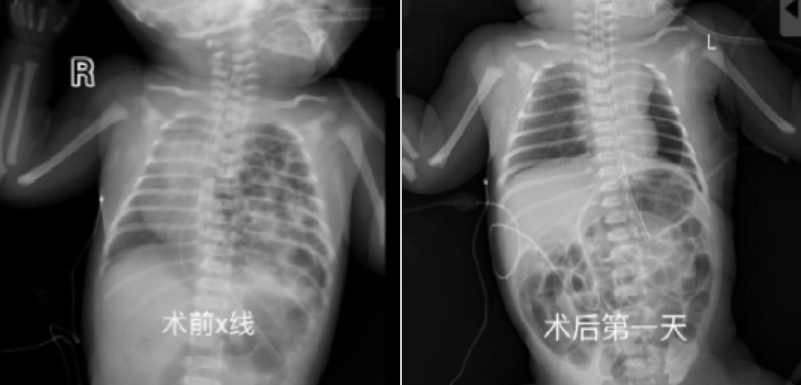

生死24小时!交大一附院多学科联动,为出生1天的“膈疝宝宝”抢回生机

近日,交大一附院小儿外科、新生儿科等多学科团队(MDT)紧密协作,成功为出生仅1天的先天性膈疝新生儿实施微创修补手术,患儿术后康复出院。先天性膈疝死亡率高,我院产检发现胎儿病情后,周熙惠、曹振杰主任牵头多学科会诊,制定“产前评估—产时干预—产后救治”一体化方案。患儿出生后呼吸困难,新生儿团队即时气管插管通气,转入新生儿科稳定病情。生后24小时,儿外科团队采用胸腔镜微创技术,克服新生儿操作空间小、脏器脆弱的难点,将疝入胸腔的脾脏、肠管还纳,并用生物补片修补巨大膈肌缺损,手术顺利完成。